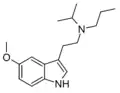

| MPT | artificial | H | CH3 | CH2CH2CH3 | N-Methyl-N-propyltryptamine | 850032-72-3 |